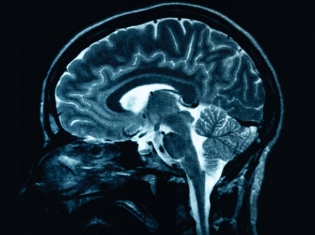

New MRI Method for Diagnosing Dementia

Alzheimers disease may be diagnosed using MRI in a new way

Researchers used magnetic resonance imaging (MRI) to estimate the amount of two proteins that build up in the brain in Alzheimer’s disease (AD). They compared the estimates to the levels found in spinal fluid tests. The MRI method gave the same diagnosis as the spinal tap about 75 percent of the time.

The researchers wanted to know if they could use an MRI to look for markers of AD – tau and beta amyloid – that would help doctors know which type of dementia a person had.

Using the MRI, the researchers looked at the brain tissue and devised a way to estimate the amount of tau and beta amyloid in the brain.